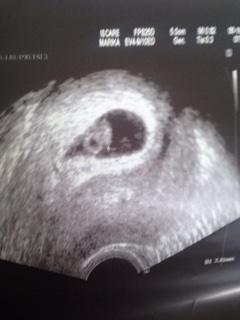

Tak já dnes začínám 8. týden...

V uterý jsem byla na kontrole, srdíčko bylo a bilo 🙂 Říkala jsem Jarže že si nepřipadám moc těhotná, říkala mi - no tak si zapamatujte, že jste těhotná, víc těhotná být nemůžete :D :D

@lagina krásný gumovy medvidek 🙂 at je ti pořad tak Dobre 🙂

@lagina miminko krásné roste 🙂